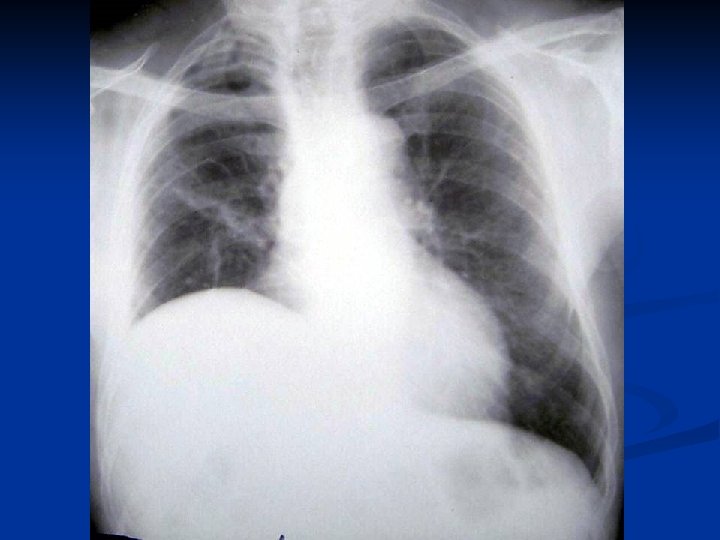

CONSIDERATII GENERALE ASUPRA CHISTULUI HIDATIC PULMONAR C. Mitrofan, A. Aldea, C. Grigorescu, I. Jitaru, C. Moldoveanu, G. Iosep, S. Bolog, M. Radulescu Clinica de Chirurgie Toracica U. M. F. Iasi

Caracteristici generale n n n Boala parazitara determinata de Taenia echinococcus granulosus. Descrisa inca de pe vremea lui Hipocrat si a lui Galen. Termenul de “chist hidatic” utilizat de Rudolphi in 1908. Localizarea pulmonara este a doua ca frecventa dupa cea hepatica. Boala cu distributie endemica in regiunea mediteraneana, Orientul Mijlociu, Australia, Noua Zeelanda, America de Sud.

Material si Metoda n Studiul de fata analizeaza retrospectiv 162 de cazuri operate in perioada 1999 – 2003.